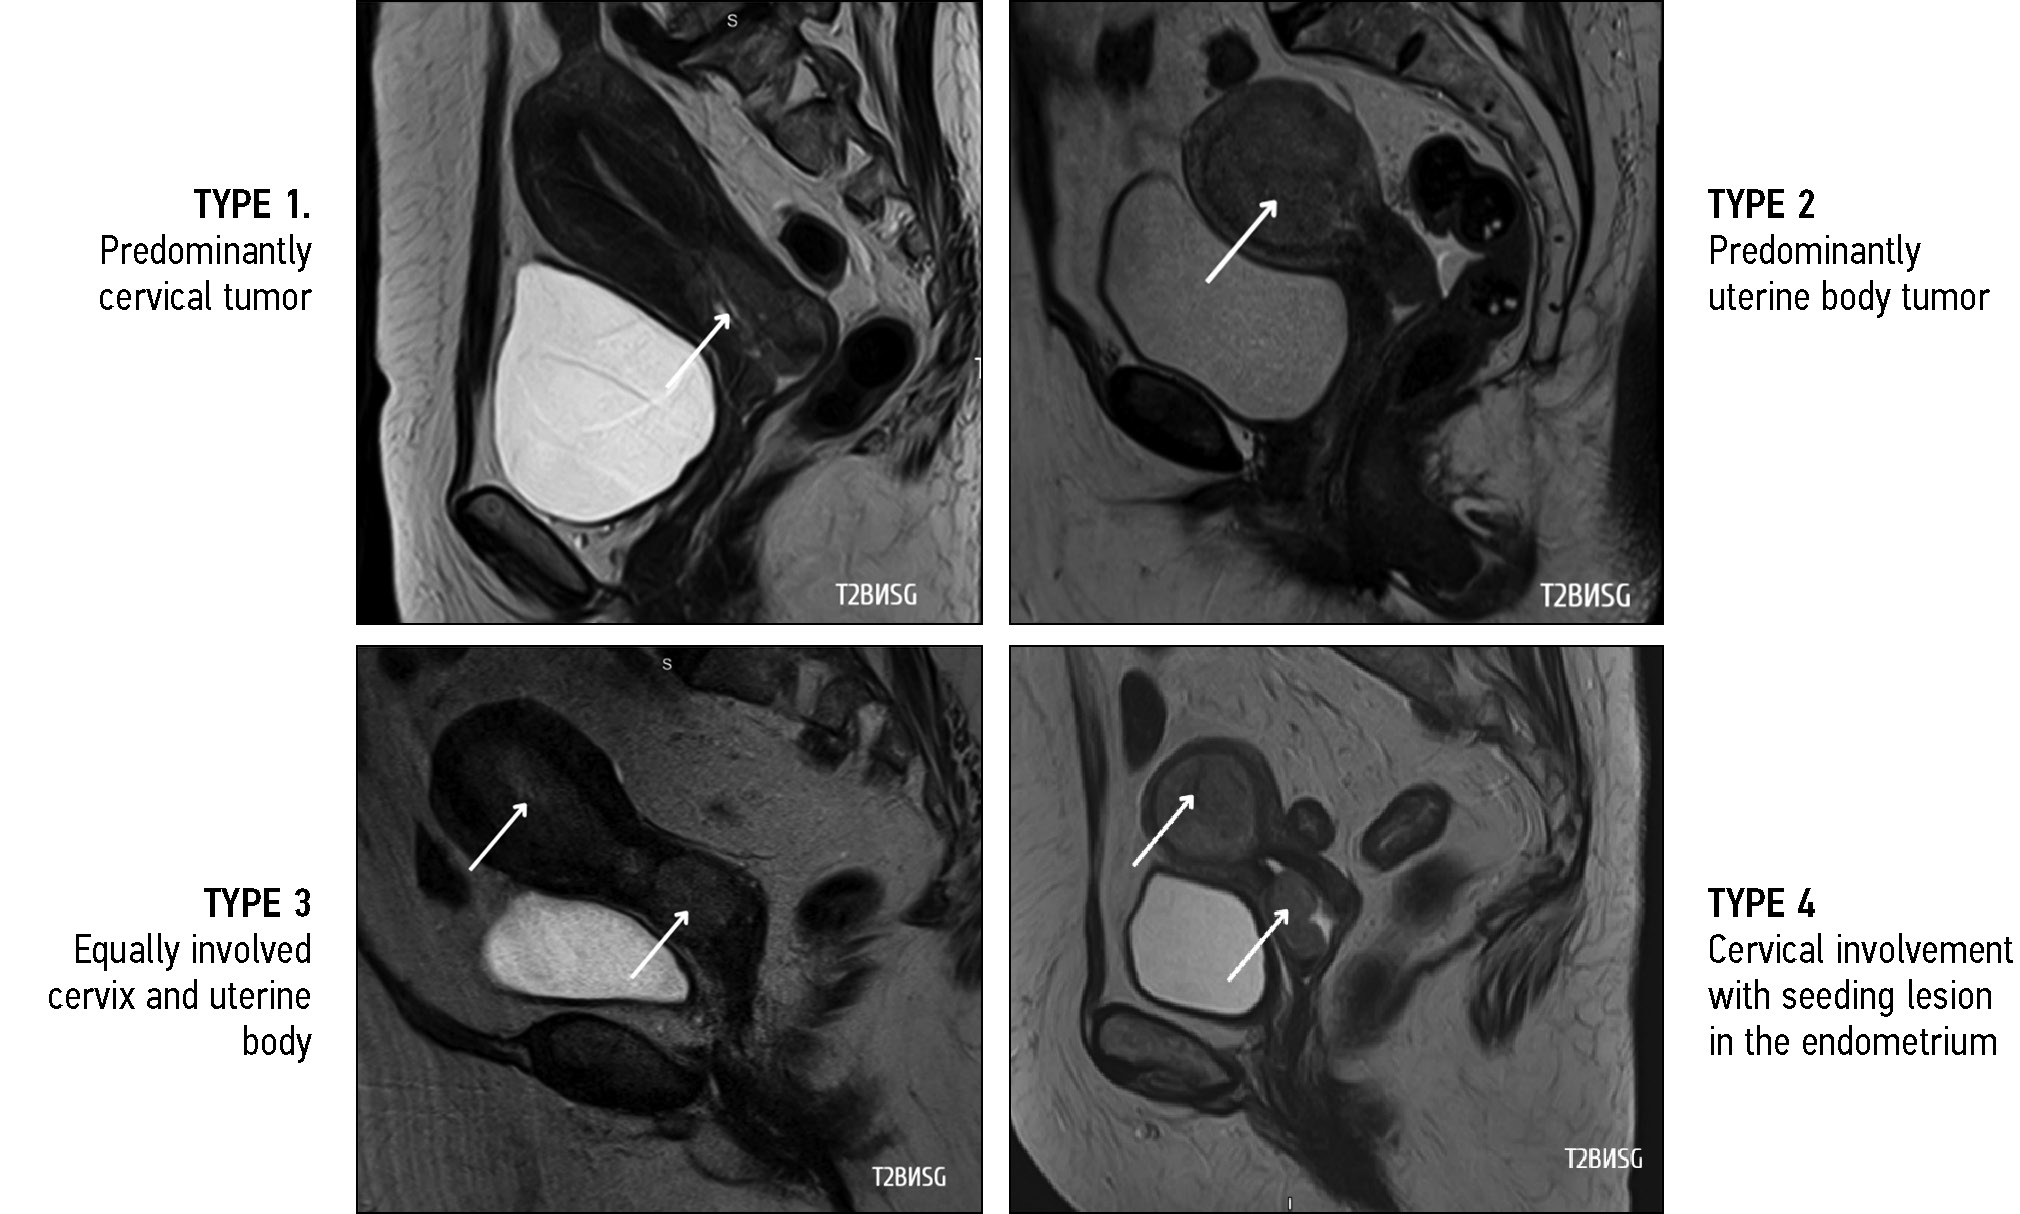

Differential diagnosis of the location of the primary tumor (whether the observed uterine abnormalities were endometrial carcinoma with cervical involvement or cervical carcinoma with endometrial involvement) was critical in the diagnostic search of gynecologists and radiologists for detecting uterine adenocarcinoma. All diagnostic controversies with predominant involvement in the uterine cavity were further reviewed by pathologists, and in all patients, endocervical adenocarcinoma (tumor of the cervix) was confirmed. Therefore, four types of tumor macrostructure were retrospectively classified based on the predominant location of the tumor according to MRI and pathology data (Fig. 4):

- Predominance of tumor in the cervix (n = 13; 65%)

- Predominance of tumor in the uterine body (n = 2; 10%)

- Equal involvement of endocervix and endometrium (n = 2; 10%)

- Isolated cervical lesion with CA lesion seeding into the uterine cavity (in the endometrium), confirmed by pathology and immunohistochemistry data (n = 3; 15%)

Fig. 4. Type of tumor macrostructure, T2-weighted images in sagittal plane, cervical adenocarcinoma.

Notably, type 2, 3, and 4 tumors were described as uterine body cancer on MRI, and only pathology examination confirmed primary CA.